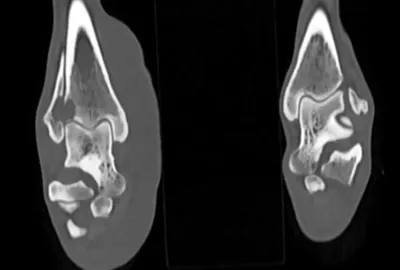

Hlava a krk:

Zobrazení a diagnostika patologií v dutině nosní (nádory, chronické záněty, cizí tělesa). Zlomeniny čelistí. Hluboké procesy v nosohltanu a krku (nasopharyngeální abscesy). Patologie v oblasti oka. Některé nádorové procesy mozku a lebky. Fraktury lebky, krvácení do mozku. Poranění krční páteře. Poranění dýchací trubice či hrtanu.